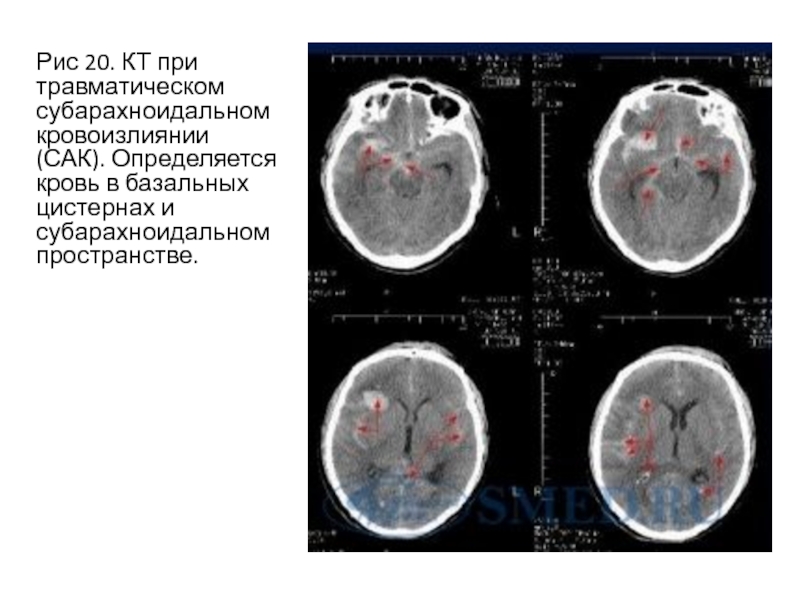

Слайд 15Рис 20. КТ при травматическом субарахноидальном кровоизлиянии (САК). Определяется кровь

в базальных цистернах и субарахноидальном пространстве.